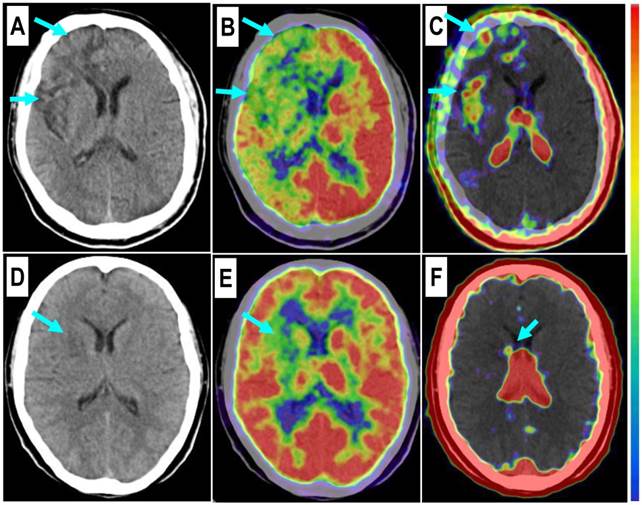

Figure 2

Comparison of a patient with slight myocardial infarction (MI) and a patient with severe MI. Upper row: In a 58-year-old man at the 5th day after the event, a small apical region with decreased 99mTc-MIBI perfusion (A, arrow) and 18F-FDG metabolism (B, arrow) showed mild 68Ga-PRGD2 accumulation (C, arrow), with a pSUV of 0.62. Lower row: In a 45-year-old woman on the 7th day after the event, an apical defect on 99mTc-MIBI perfusion images (D, arrow) and 18F-FDG metabolism images (E, arrow) corresponded with moderate 68Ga-PRGD2 uptake (F, arrows), with a pSUV of 2.02.

In this group of patients, higher 68Ga-PRGD2 uptake was found approximately 1 week after the MI event and remained high in the patients 2.5 months post-MI (Figure 3). In 15 MI patients within 4-75 days after the attack when the 68Ga-PRGD2 uptake seemed to be in a plateau (Figure 3), the uptake levels were significantly correlated with the maximum diameters of the infarction regions measured on the 99mTc-MIBI cardiac perfusion imaging (r=0.748, P=0.001) (Figures 2 and 4).

Among the three patients without significant 68Ga-PRGD2 accumulation at the cardiac region, one patient was on the third day after a slight MI attack without ST-elevation on the ECG, whereas the other two patients were 1-2 years post-MI without any related symptoms (Figure 1 C and D).